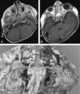

Visceral neuropathy - brain anomalies - facial dysmorphism - developmental delay